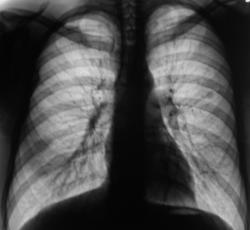

Образование верхней доли левого легкого с дорожкой к корню, мне кажется может оказаться как периферическим раком ,так и туберкуломой.Надо начать с линейной томограммы. А нет ли вздутия переднего отрезка 3 ребра?

Этот дефект на всех снимках - это наше "факсимиле" - шутка. Дефект на экране, мы с ним уже смирились. Мы тоже подумали о периферическим раке и "дорожку" приняли к сведению. По поводу туберкулёза, как - то не подумали. Конечно, и о доброкачественной опухоли также вспомнили. Конечно, все "большие симпатии" в векторе периферического рака лёгкого.

И все таки похоже на туберкулому, мне кажется за год несколько уплотнилось образование, были более четкие,ровные контуры, а сейчас какбы чуть-чуть сжалось(или выдаю желаемое за действительное?). Просто у меня был очень похожий случай,только в нижней доле левого легкого за тенью сердца, с дорожкой к корню с лучистыми (как мне казалось)контурами образование чуть больше вашего,была уверена , что периферический рак, а больной сйчас в туб.диспансере лечит туберкулому.

А ещё смущает некоторое неоднородность, даже какие то плотные включения, межет это конечно сосуды накладываются.  Валентин Львович, у Вас же наверное где то томограмка завалялась?

Кстати, а такое образование ещё может соответствовать сосудистой мальформации, другое дело, что если раньше этого небыло. А если сравнивать от 2008г. так без динамики.

Я не думаю, что Вас "глючит", так как Вас просто "не может глючить". Я тогда, в 2007 году, "повязал" скиалогическую картину справа на уровне 1 ребра справа, и наличие овальной формы тени средней интенсивности слева в 3 межреберье. Один из наших уважаемых пользователей, сказал как-то, что я "постоянно заточен на туберкулёз", и это правильно, с учетом "нашей эпидситуации". Так вот тогда, я с большим скрипом и неудовольствием, высказался в пользу специфического процесса, хорошо понимая, что данных весьма мало.

А на боковой рентгенограмме, вроде-бы кропноочаговая тень не одна? А вроде-бы две?